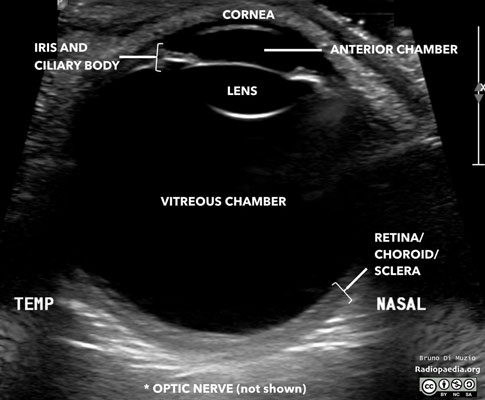

An eye and orbit ultrasound is a test to look at the eye area. It also measures the size and structures of the eye.

The ultrasound uses high-frequency sound waves that travel through the eye. Reflections (echoes) of the sound waves form a picture of the structure of the eye. The test takes about 15 minutes.